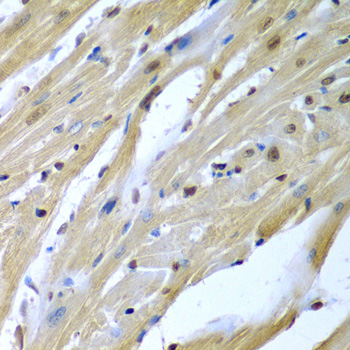

Immunohistochemistry of paraffin-embedded mouse heart using TUSC2 antibody.